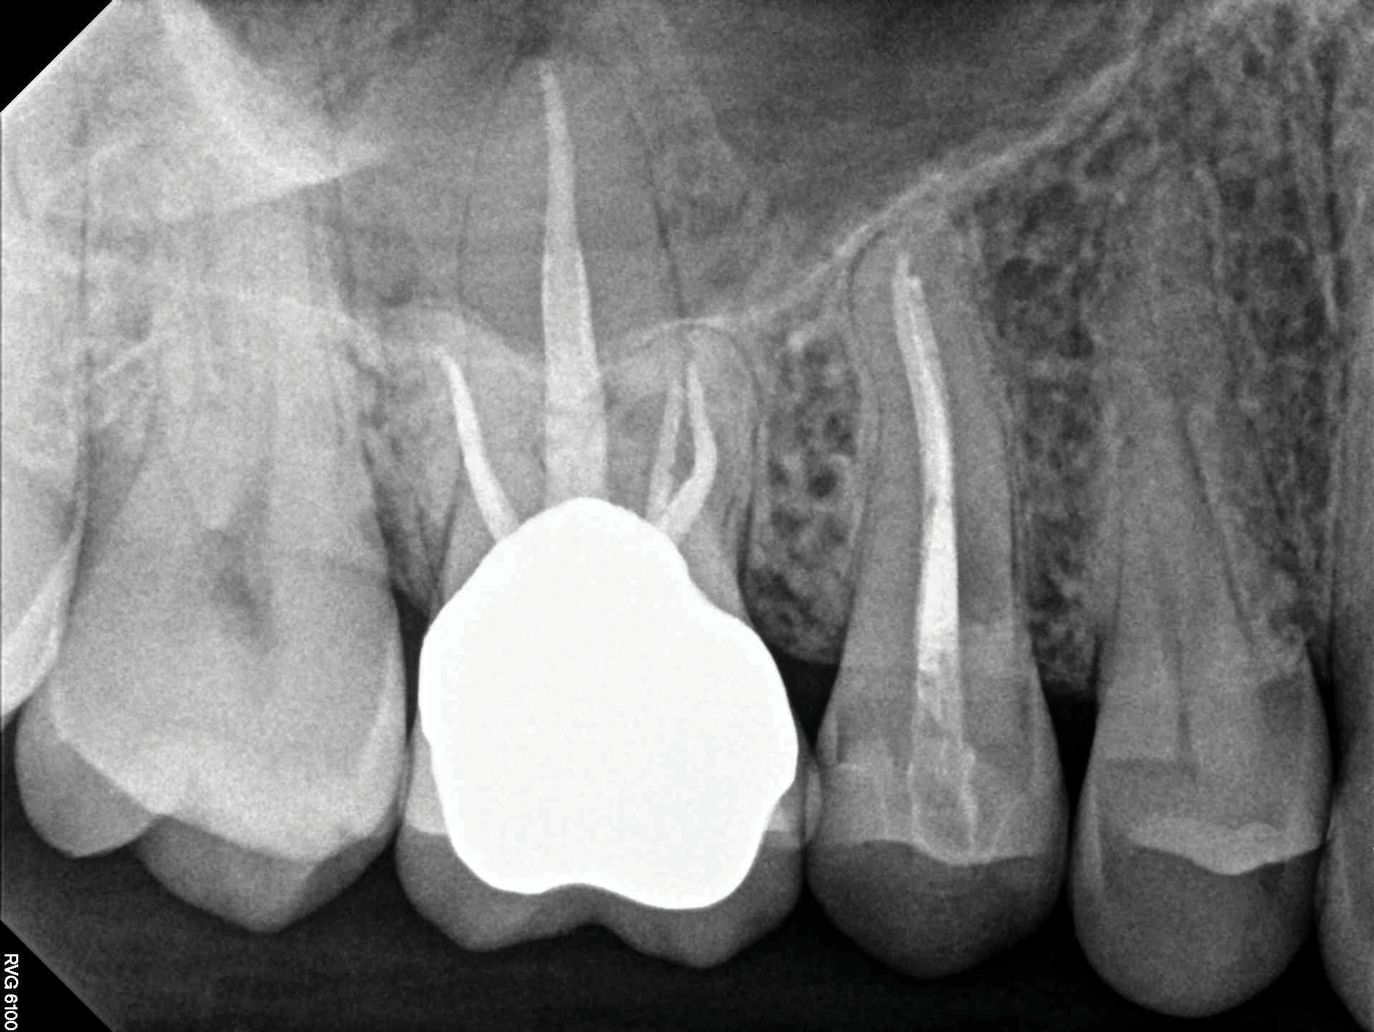

(1.) Preoperative CBCT scan showing Class 2 ECR defects on teeth Nos. 3 and 4 that were surgically accessible.

Figure 1

(2.) NSRCT, which had previously been completed on tooth No. 3, was also completed on tooth No. 4 prior to initiating surgical repair of the ECR lesions because it exhibited signs and symptoms of irreversible pulpitis.

Figure 2

(3.) The initial surgical exposure revealed defects coronal to the crestal bone that were filled with granulation tissue and consistent with ECR.

Figure 3

If an ECR lesion is surgically accessible, external repair with gingival flap surgery is the treatment of choice (Figure 1 through Figure 6). When considering external repair, clinicians should evaluate each case for potential postoperative esthetic concerns, such as the possibility of recession following surgical repair.6,7 Moreover, clinicians should assess the overall restorability of affected teeth because the surgical repair of large ECR lesions may predispose them to fracture.6 When a Heithersay Class 1 lesion is diagnosed, nonsurgical root canal therapy (NSRCT) in addition to the surgical repair is often unnecessary. However, in Heithersay Class 2 or larger defects where pulpal involvement is suspected or confirmed, NSRCT may be necessary in addition to surgical repair.6 If NSRCT is indicated in addition to surgical repair, it is recommended that it be completed prior to surgery to avoid exacerbating pulpal disease.